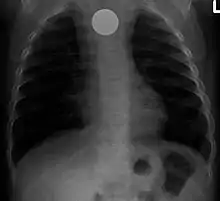

Un corps étranger (pièce de monnaie) dans l’œsophage.

- (Médecine) Objet de taille au moins d’un millimètre et qui a pénétré le corps humain ou animal.